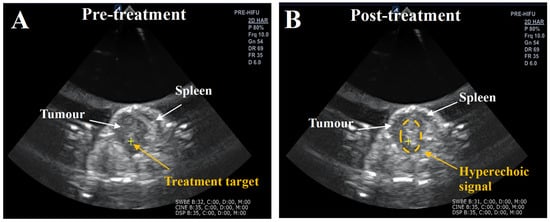

| Subject | Number of Exposure Positions per Tumour | Number of Exposure Pulses per Tumour | Percentage of HH-Positive Exposure Pulses (%) | Number of HH Positive Exposure Pulses per Tumour | Percentage of Broadband Signal Exposure Positive Pulses (%) | Number of Broadband-Positive Exposure Pulses per Tumour | Hyper-Echoic Signals |

| BH- Subject 1 | 28 | 660 | 98 | 650 | 14 | 95 | Yes |

| BH 2- Subject 2 | 17 | 350 | 100 | 350 | 94 | 330 | Yes |

| BH 3- Subject 3 | 30 | 720 | 100 | 720 | 20 | 150 | In-conclusive |

| BH 4- Subject 4 | 19 | 450 | 100 | 450 | 77 | 345 | Yes |

| BH 5- Subject 5 | 25 | 535 | 100 | 535 | 67 | 360 | Yes |

| Comb 1- Subject 1 | 13 | 310 | 97 | 300 | 100 | 310 | Yes |

| Comb 2- Subject 2 | 10 | 230 | 91 | 210 | 95 | 220 | Yes |

| Comb 3- Subject 3 | 22 | 530 | 100 | 530 | 4 | 20 | Yes |

| Comb 4- Subject 4 | 17 | 350 | 100 | 350 | 2 | 6 | Yes |